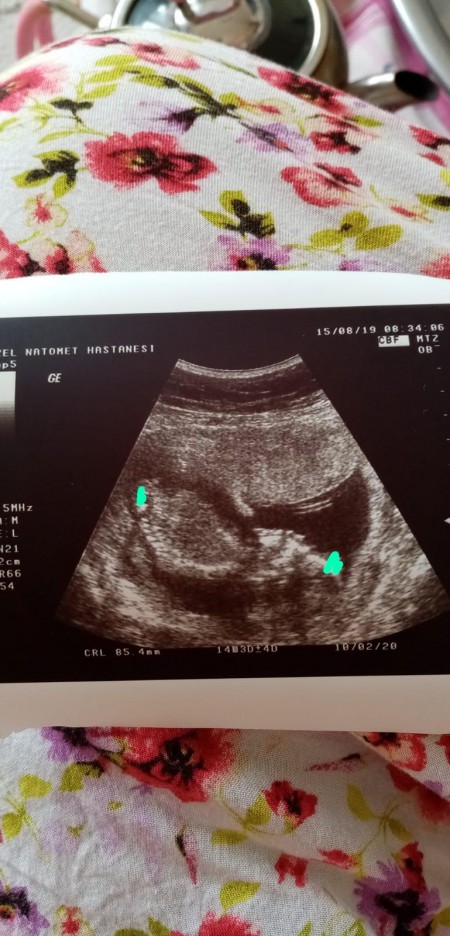

Sizce nedir kızlar

image